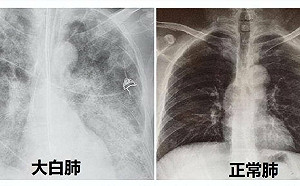

那跟什麼有關? 「大白肺現象」瘋傳 北京「闢謠」:與原毒株、疫苗接種無關